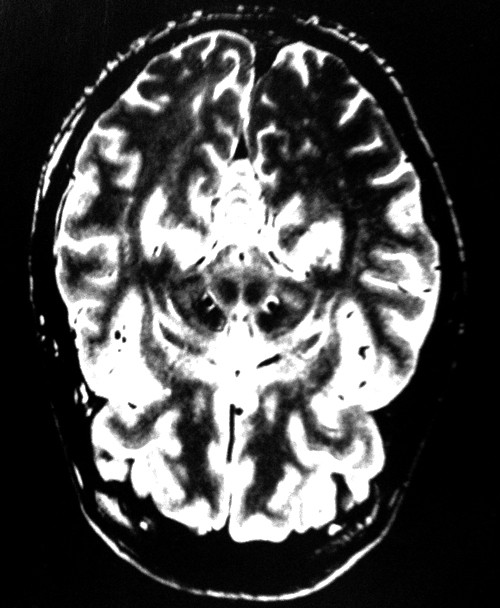

I mention this because just recently (as a long term user of Leva Dopa the main anti Parkinsons drug, whose side effects include hallucinations ) I’ve been getting them too and and it is very wierd. I als often get the the feeling that somebody is always behind my shoulder. Also, any small bits of detritus, crumbs etc will often appear to my cauliflower brain as scuttling little insects.